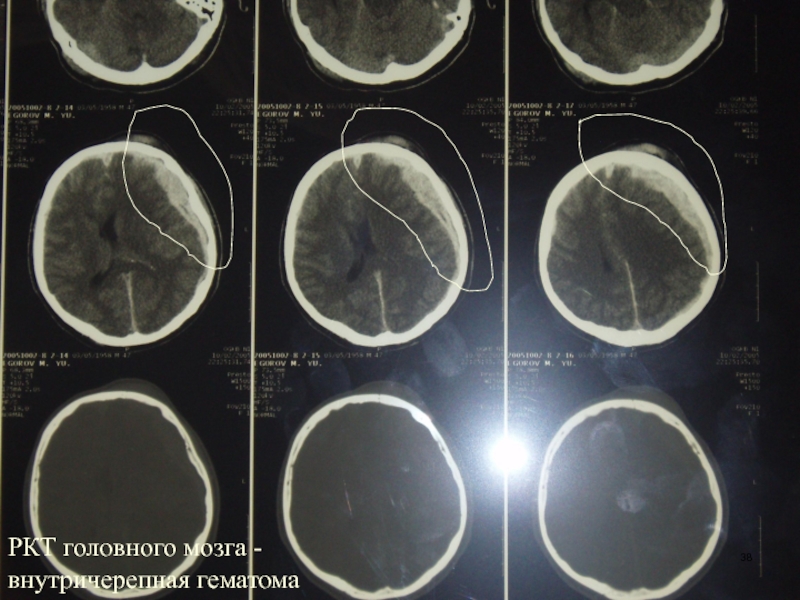

Слайд 38РКТ головного мозга - внутричерепная гематома

РКТ головного мозга - внутричерепная гематома